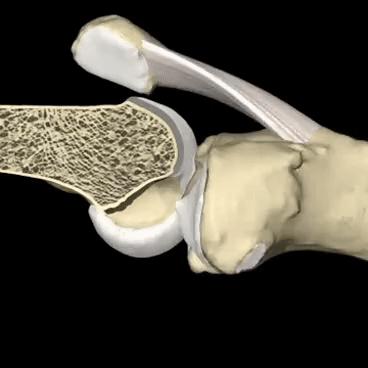

髌骨软骨软化,诱发这种情况最常见的原因。

诱发髌骨软骨软化的原因是非常多的,主要见于长时间的过度使用、剧烈运动、长时间爬山比如有一些朋友特别喜欢长时间的盘腿,或者工作经常要做蹲起这样的动作,在屈伸关节的过程当中就会增加髌骨以及后方股骨之间的压力,导致髌骨软骨发生退变。

出现髌骨软骨软化早期的症状,主要是上下楼梯时的疼痛以及屈伸关节时候的沙沙的响声,一般不会有特别的疼痛,只有当症状进一步加重,关节腔的软骨磨损越来越严重以后,才会伴有明显的疼痛。

另外髌骨软骨软化比较经典的症状就是打软腿了。在走路的时候并没有什么特殊的诱因,膝盖会突然软一下,仿佛失去了对膝盖的控制一样。这个时候往往并不伴有疼痛,所以也很少有人在意,但是当症状越来越重,出现疼痛的时候再进行治疗可能就错过了治疗的最佳时机了!下图就是髌骨软骨不同程度软化的关节镜下影像学资料,看完之后,大家可能会对这个问题有一个更深的了解吧。

明确关节腔是否有软骨软化,主要靠医生的查体、患者的症状,另外需要进行膝关节核磁检查,因为软骨在x线下是不显影的,只有核磁才能看到关节腔内软骨的具体情况。

髌骨软骨软化早期的治疗可以口服氨糖,或者是给予关节腔内注射玻璃酸钠,来增加关节软骨的弹性,减轻患者的症状,有点类似于我们给磨损的自行车轴承上黄甘油一样。

另外对于膝关节髌骨软化的治疗,强化股4头肌的力量,具有非常好的作用,在文章的最后我会给大家进行一个详细的介绍。